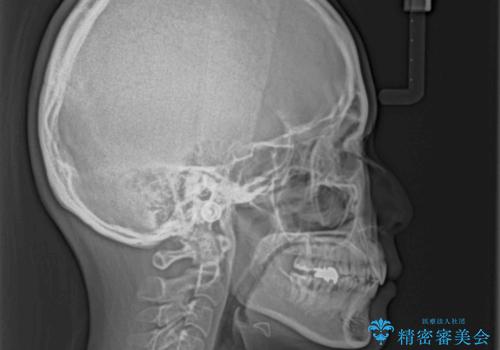

- 口元の突出感と口の閉じにくさを気にして来院された患者様です。

上下左右第一小臼歯4本を抜歯し、ワイヤー装置にて口元を引っ込めるよう矯正治療を行うこととしました。

ご友人などがびっくりするほど口元の突出感を改善することができ、患者様には大変満足していただきました。